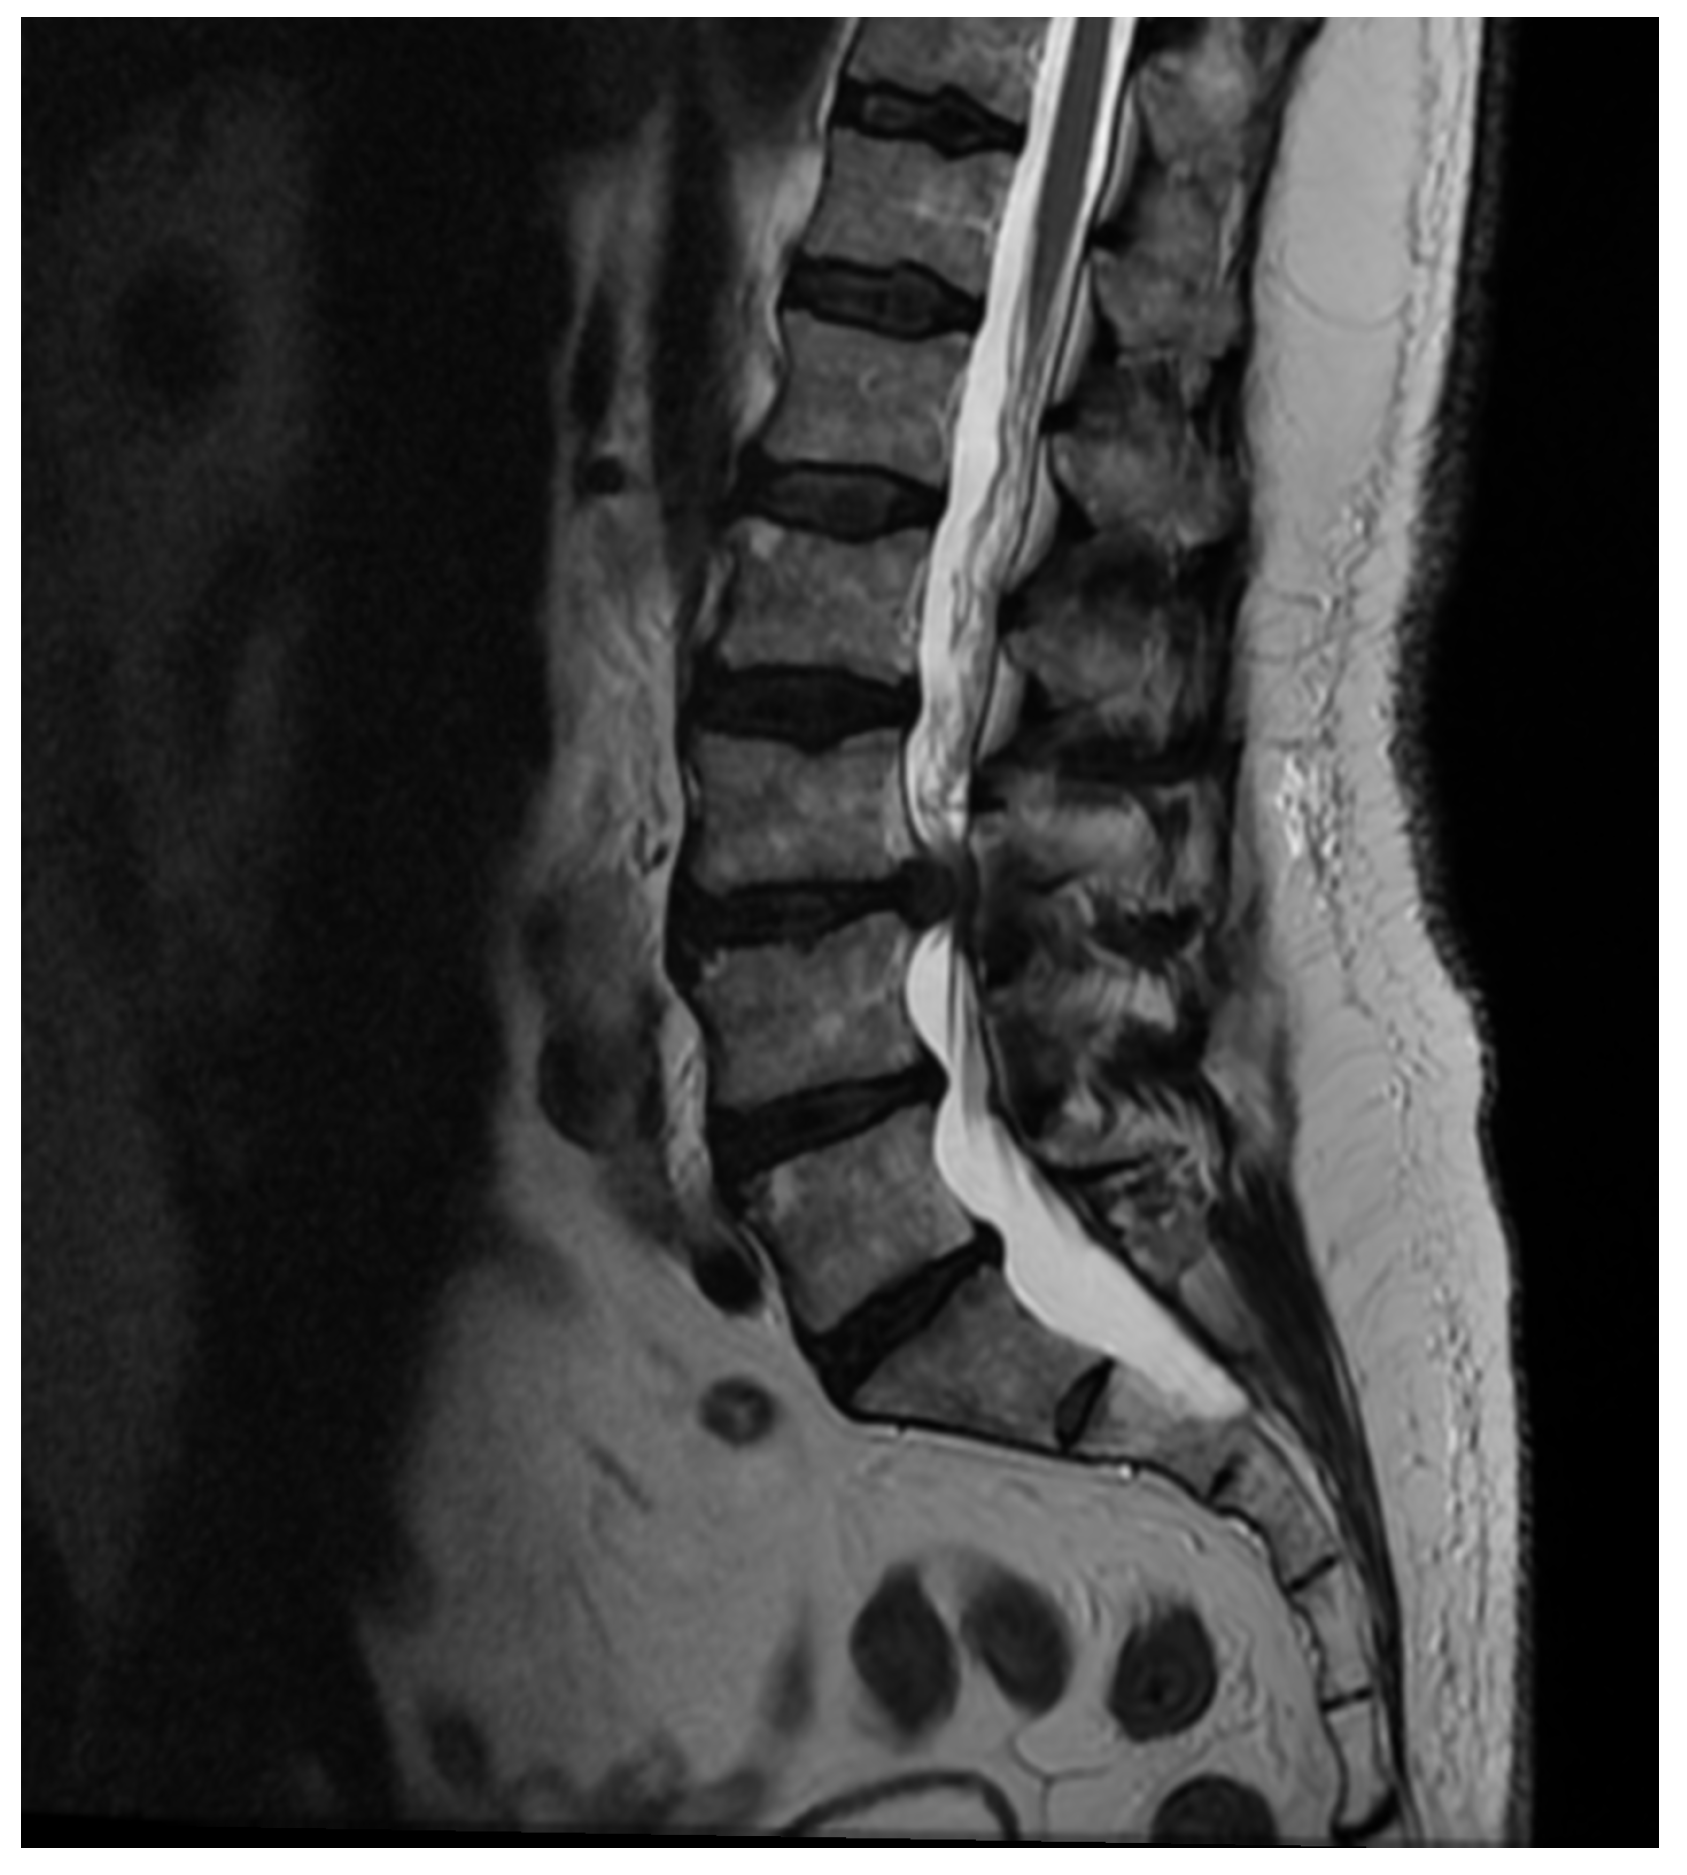

Patient Background: A 70-year-old male patient with a history of diabetes and chronic renal failure was scheduled for surgical treatment of discopathy at the L3/L4 level (Figure 6). The patient underwent microdiscectomy using a minimally invasive access retractor Spotlight (Johnson and Johnson, New Brunswick, NJ, USA).

Further Intervention: Another MRI confirmed that despite extensive decompression, significant narrowing persisted at the operated level, with a markedly increased T2 signal in the disc space (Figure 7). A subsequent endoscopic transforaminal approach was employed. Inflammatory disc material and granulation tissue from the spinal canal were removed. Post-operative MRI showed a satisfactory degree of decompression of the canal. The patient was mobilized and transferred to the nephrology department due to further deterioration of renal function.

Figure 6. Pre-operative T2 sagittal MRI image at the L3/L4.

Figure 7. T2 axial MRI image at the L4/L5 level following previous open surgical treatment.